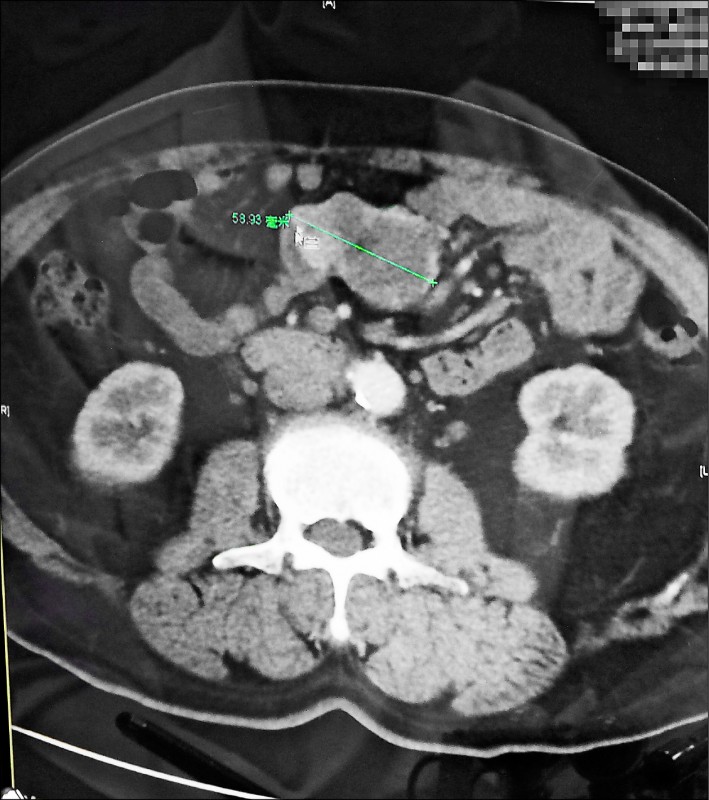

一名男子車禍受傷送醫,急診醫師擔心腹內器官損傷,安排他接受電腦斷層掃描,意外發

現其小腸有一顆5.6公分的腫瘤。經手術切除後化驗,病理報告顯示為罕見的胃腸道基質

瘤。

58歲黃姓男子上月發生車禍受傷,被送到草屯鎮佑民醫院救治,由於腹部有挫傷、四肢有

多處擦傷,急診室醫師擔心腹內器官損傷,為他做了腹部電腦斷層掃描,意外掃描出小腸

有5.6公分的腫瘤;轉介至一般外科醫師林佳正門診,黃男接受醫師建議切除腫瘤。

手術後病理報告顯示為罕見的「胃腸道基質瘤」,每100萬人中,每年僅10至20個病例。